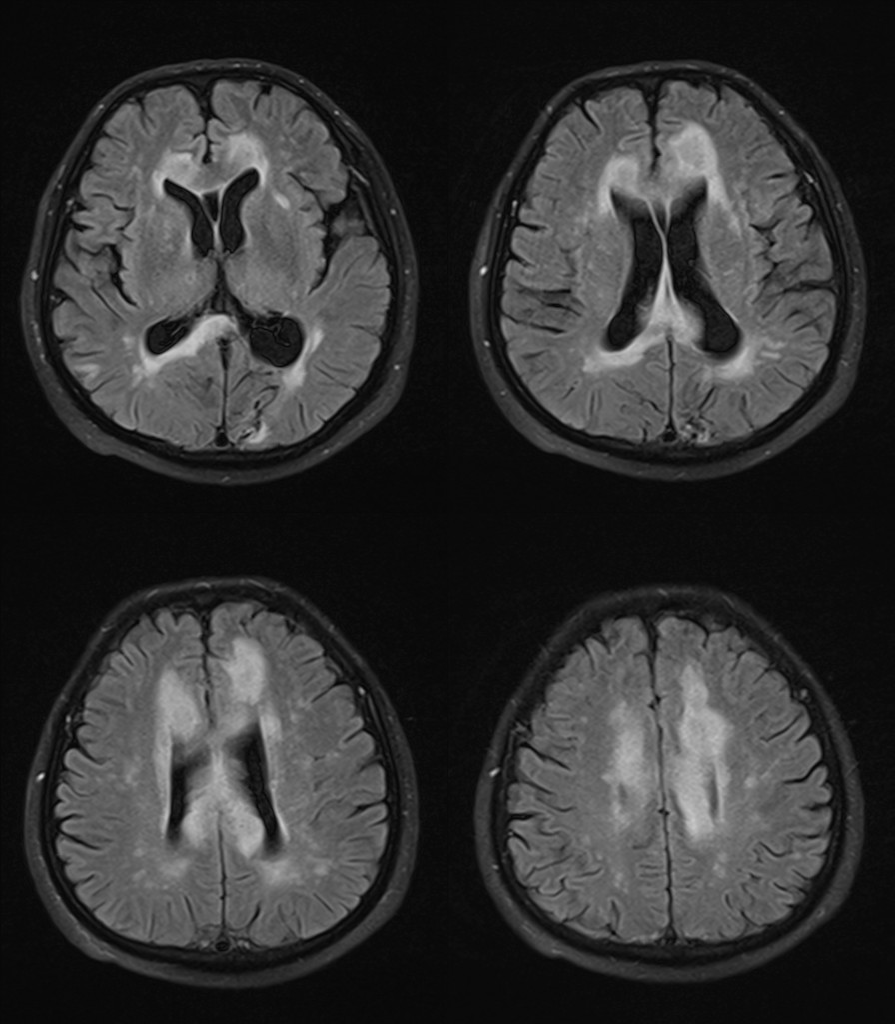

影像资料:

•急性期表现为胼胝体弥漫性肿胀,T1WI呈稍低信号,T2WI及FLAIR呈稍高信号,以矢状位观察最佳,可单独累及胼胝体压部或整个胼胝体,DWI呈高信号,ADC图呈低信号,部分患者可观察到脑室周围白质或内囊受累,少见皮层受累,表现为扩散受限,不强化和强化病例均可见到。如果增强扫描可见胼胝体有不同程度强化,呈小灶状或不规则斑片状,系血脑屏障破坏所致(如本例),本例患者处于急性期。

上排:原发性胼胝体变性急性期

下排:原发性胼胝体变性慢性期,表现为胼胝体萎缩、软化